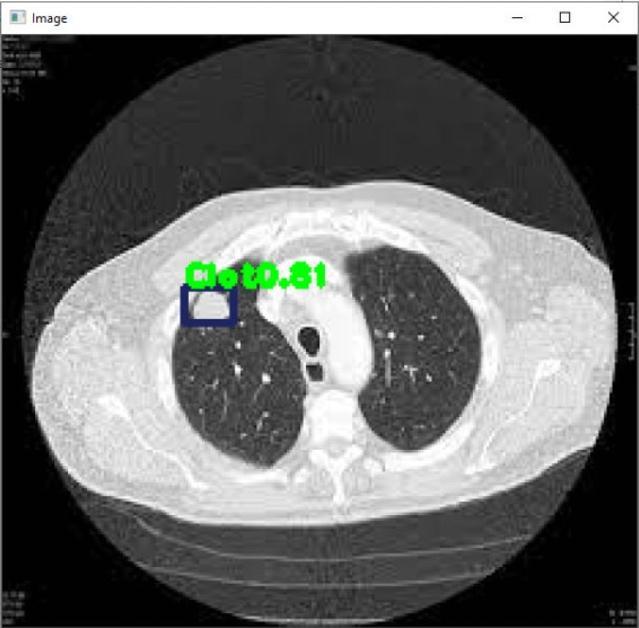

Fig 3 :TomorDetectedinLungs Fig 4 :ClotDetectioninLung Fig 4 :Clot&TumorDetectioninLung Fig – 5 :TumorDetectioninLung

finaloutcome.